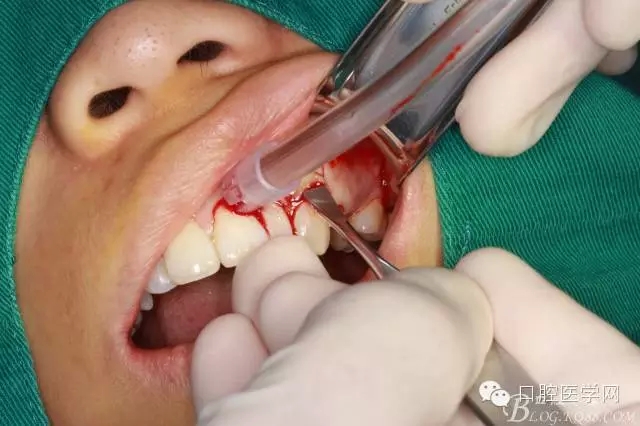

局部浸潤麻醉

齦乳頭麻醉

鼻腭神經(jīng)麻醉

垂直切口

水平切口